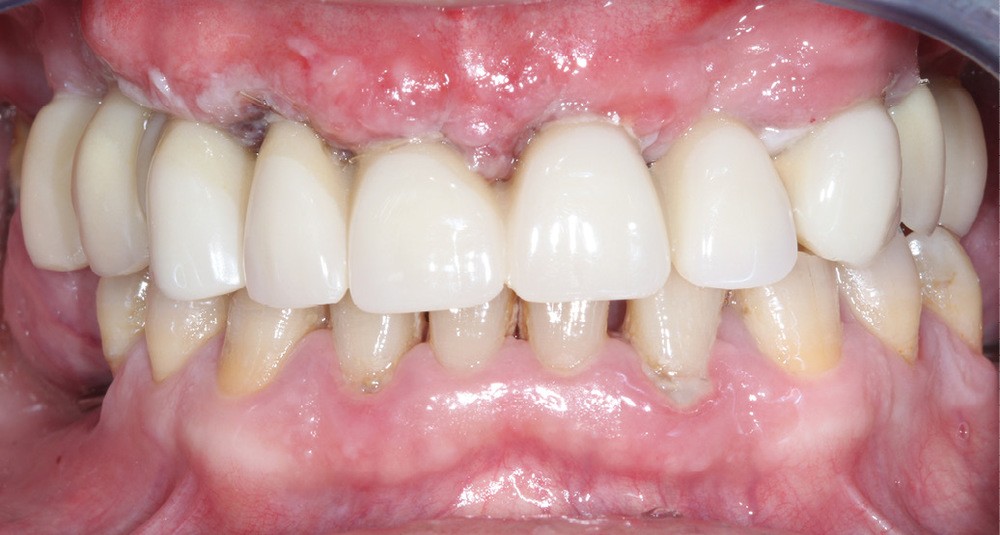

Réévaluation (mars 2022)

Le patient a été satisfait de l’immédiateté et du confort de la restauration provisoire, mais n’a malheureusement pas poursuivi son traitement et n’est venu consulter que quelques années plus tard, avec des répercussions prévisibles et néfastes. L’absence de calage molaire, l’hygiène déficiente (aucun passage de brossette dans les embrasures) et une absence de suivi au cabinet ont entraîné une inflammation très importante des tissus péri-implantaires (fig. 8…